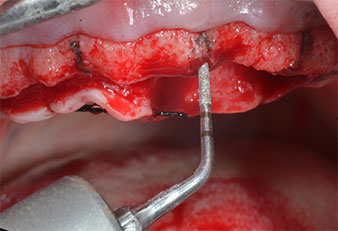

Chirurgisches Instrument Piezomed

Abb. 4: Der nächste Schritt ist die initiale Erweiterung mit den Instrumenten Piezomed I2A/I2P, die in einer horizontalen Drehbewegung verwendet werden.